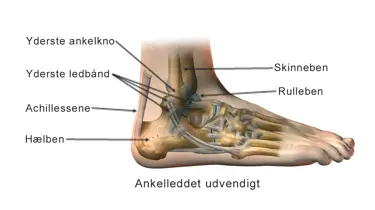

Ankelsmerter

Ankelsmerter – få hurtig hjælp hos Aleris

Smerter i anklen opstår ofte i forbindelse med sport eller fysisk aktivitet. Det kan være overbelastning, forstuvninger eller kroniske skader som slidgigt i anklen eller leddegigt. Uanset årsagen hjælper vi dig hurtigt og effektivt videre.

Hvis du har smerter i anklen, kan vores erfarne specialister med brug af MR-scanning, røntgen, ultralydsscanning og en kikkertundersøgelse hurtigt stille en præcis diagnose.

Hos Aleris møder du erfarne specialister i ankelkirurgi. Med hurtig adgang til MR-scanning, røntgen, ultralydsscanning og evt. kikkertundersøgelse (artroskopi) kan vi stille en præcis diagnose og planlægge den rette behandling for dig.